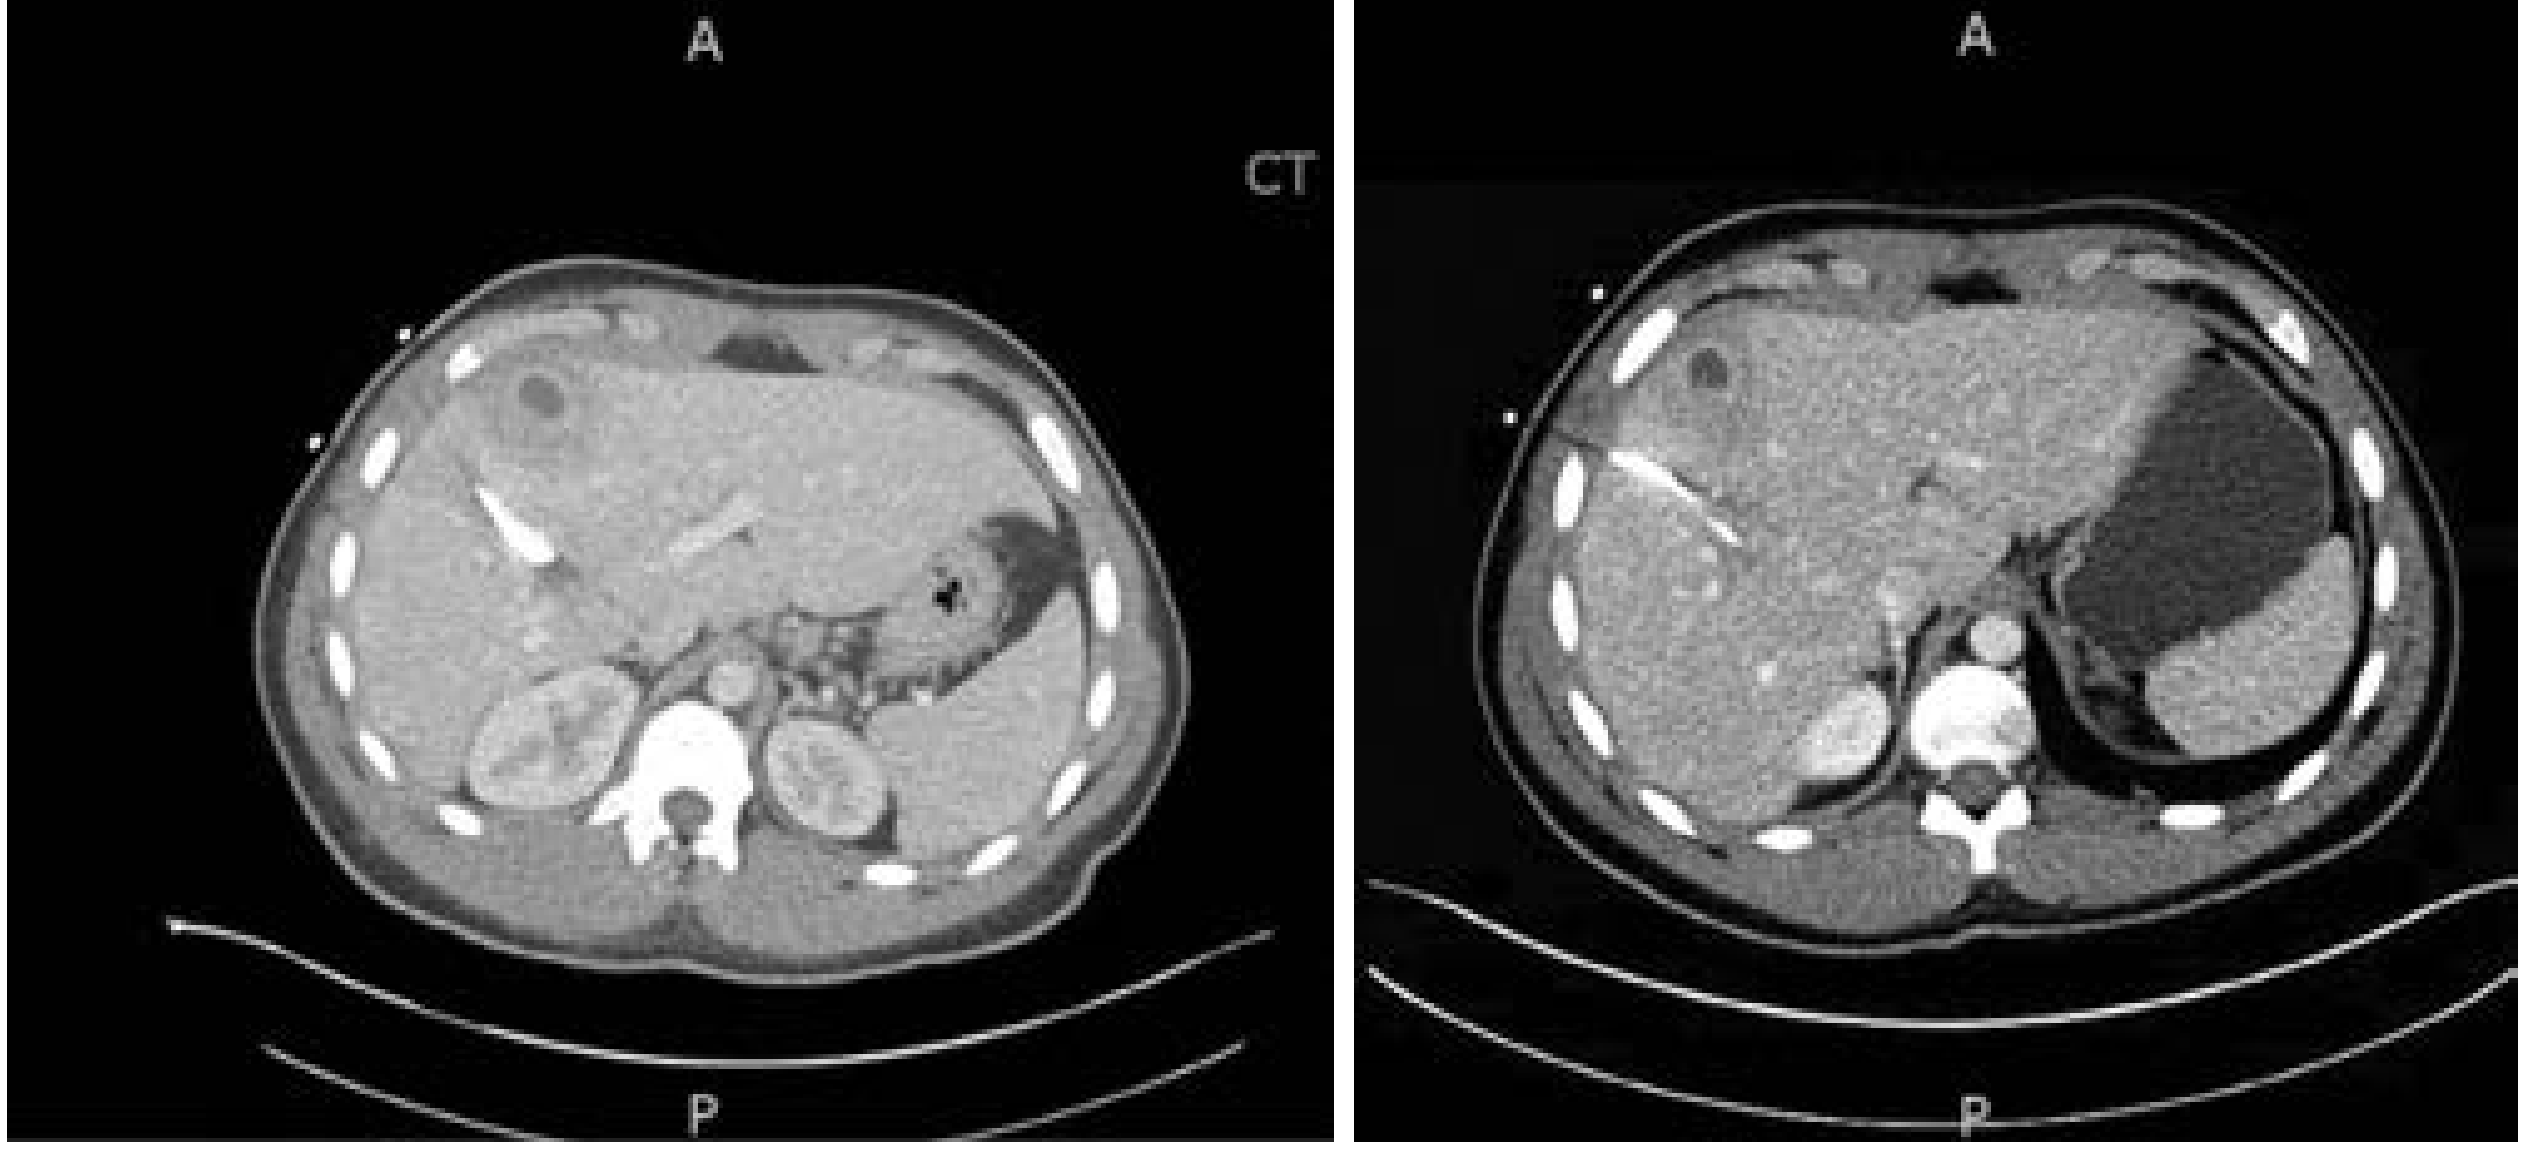

CT showing pyogenic liver abscess with rim enhancement:

CT images showing liver abscess with rim enhancement

CT images showing liver abscess with peripheral rim enhancement — Current Surgical Therapy 14e